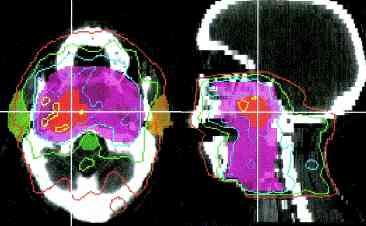

radiation isodose #1 , #2, #3, #4, #5 |